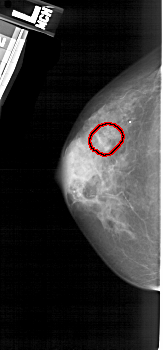

FILE: A_1937_1.LEFT_CC.OVERLAY

TOTAL_ABNORMALITIES 1

ABNORMALITY 1

LESION_TYPE CALCIFICATION TYPE PLEOMORPHIC DISTRIBUTION CLUSTERED

ASSESSMENT 4

SUBTLETY 3

PATHOLOGY BENIGN

TOTAL_OUTLINES 1

A_1937_1.RIGHT_CC

RIGHT_MLO LINES 5491 PIXELS_PER_LINE 2251 BITS_PER_PIXEL 12 RESOLUTION 43.5 NON_OVERLAY